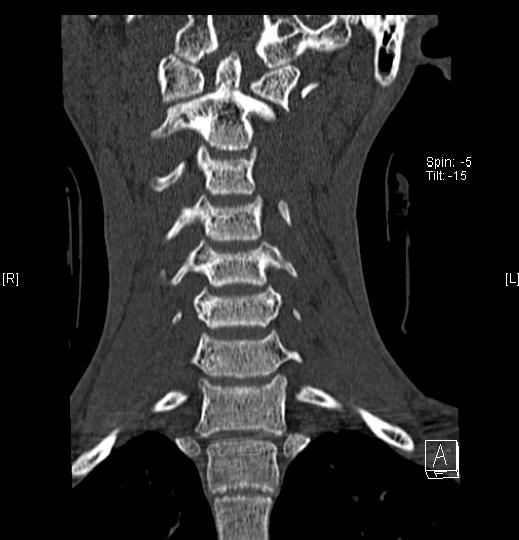

Dens Fx, Sagittal Alignment, and Impact Professionally Integrated Care What Is A Dens Fx Odontoid fractures are relatively common fractures of the c2 (axis) dens that can be seen in low energy falls in elderly patients. Odontoid process fracture, also known as a peg or dens fracture, occurs where there is a fracture through the odontoid process. We will briefly explain what a den's fracture is, how an odontoid fracture is diagnosed, different ways. What Is A Dens Fx.